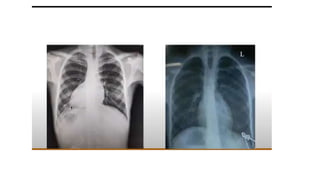

Tetralogy of Fallot

BOOT SHAPED SIGN

Tetralogy ofFallot

• 10%–11% of cases of congenital heart disease

• As a result of single defect, an anterior malalignment of the

conal septum

• Components:

• Ventricular septal defect

• Infundibular pulmonary stenosis

• Overriding aorta

• Right ventricular hypertrophy.

• Heart has the shape of a wooden shoe or boot

• Blood flow to the lungs is usually reduced

Tetralogy ofFallot • 10%–11%of cases of congenital heart disease • As a result of single defect, an anterior malalignment of the conal septum • Components: • Ventricular septal defect • Infundibular pulmonary stenosis • Overriding aorta • Right ventricular hypertrophy. • Heart has the shape of a wooden shoe or boot • Blood flow to the lungs is usually reduced